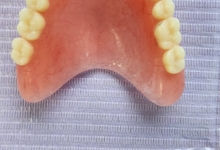

SUPRAPROTEZAREA PE IMPLANT